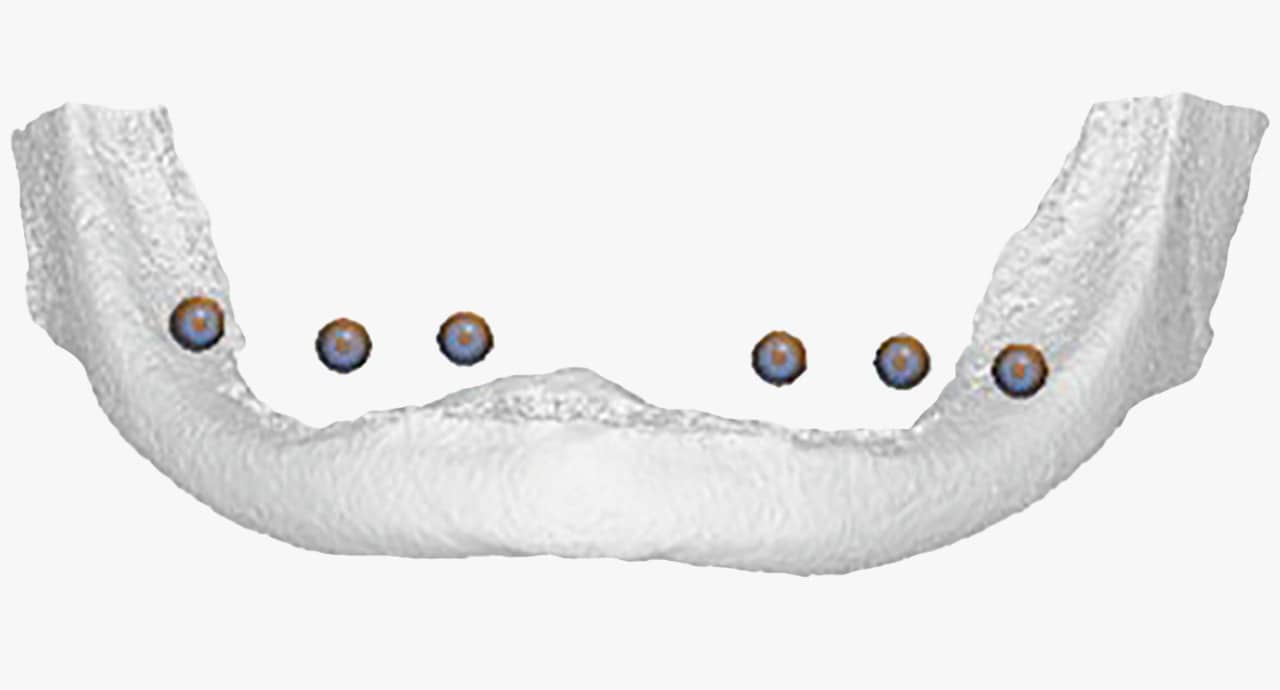

Cirurgia Guiada por Dr. João Marcelo Arcoverde

Adepto à filosofia de trabalho de que menos é mais, Dr. João Marcelo Arcoverde se tornou pioneiro no Brasil ao unir a técnica que permite repor dentes perdidos sem a necessidade de cortes e uso de bisturi convencional que diminuem drasticamente a necessidade de enxertos ósseos.

A Cirurgia Guiada é uma técnica inovadora, cujo implante dentário é feito sem cortes e pontos, portanto gerando maior conforto ao paciente, seja na reposição de um dente, de vários ou de todos.